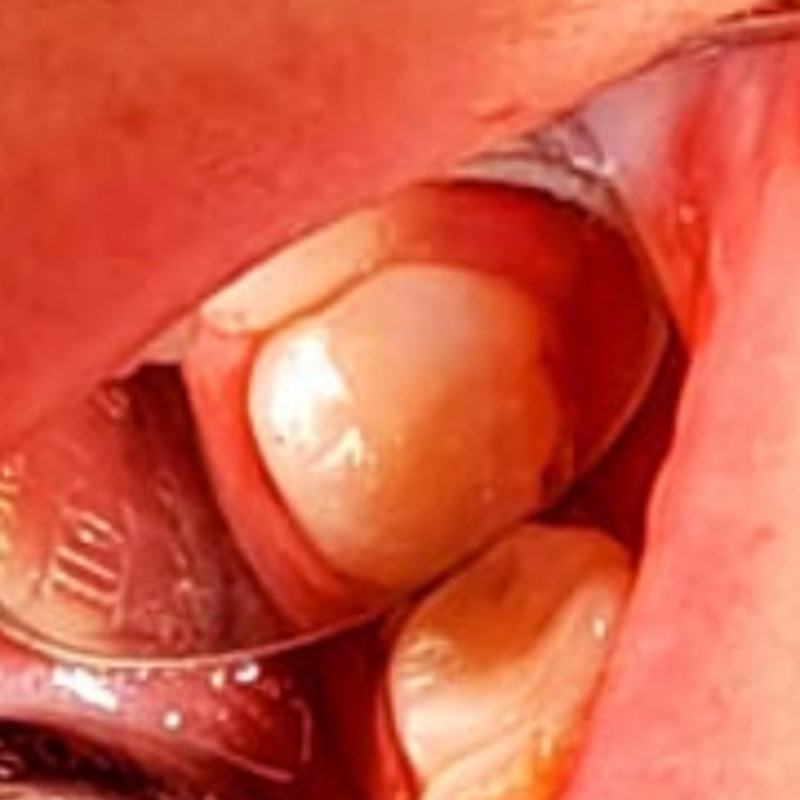

В нашу клинику обратилась пациентка с целью восстановления зубов на верхней и нижней челюстях.

После осмотра и тщательной диагностики врач-ортопед, хирург Мельников Алексей Владимирович предложил протезирование съёмными протезами с опорой на 2-х предварительно вживлённых дентальных имплантах.

- установка имплантов системы Ankylos Германия для опоры съёмного протеза по 2 на каждую челюсть;